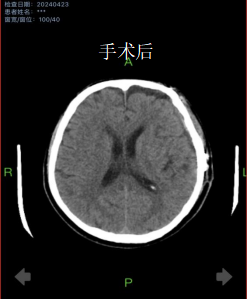

4月初,81岁的齐爷爷不慎从床上跌落,家人发现时已意识不清,急送医院就诊。完善CT检查后提示重度颅脑损伤,左侧大量硬膜下血肿。手术指征明确,由于患者病情危重,随时有呼吸心跳骤停可能,神经外科二病区主任姚胜及主治医生朱奕儒评估病情后,立即为患者行开颅手术。术后,护理团队为老人提供了优质、温馨的护理服务,齐爷爷在昏迷几天后逐渐清醒,没有留下肢体、语言等方面后遗症,痊愈出院。